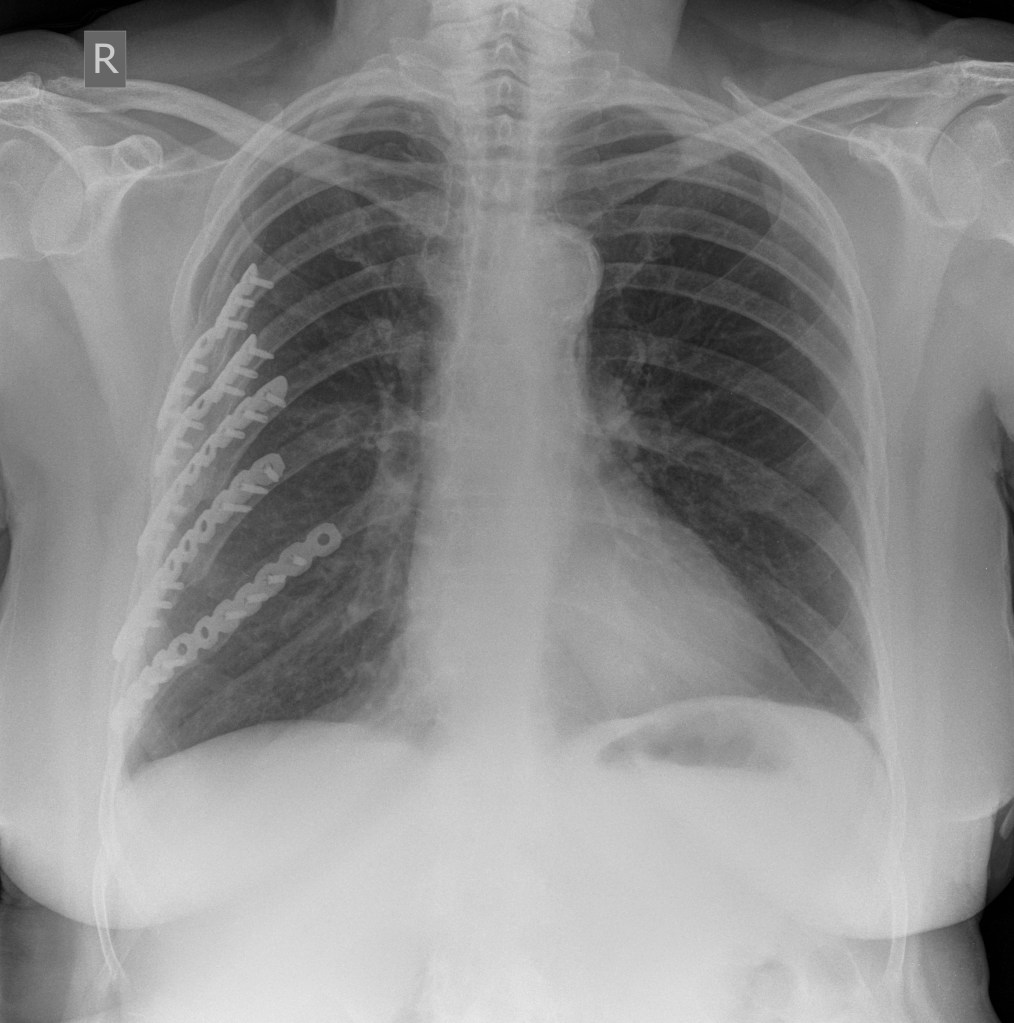

Images courtesy of Dr Jens Christian Fischer, Radiopaedia.org. From the case rID: 12821 and Dr Ian Bickle, Radiopaedia.org. From the case rID: 33585